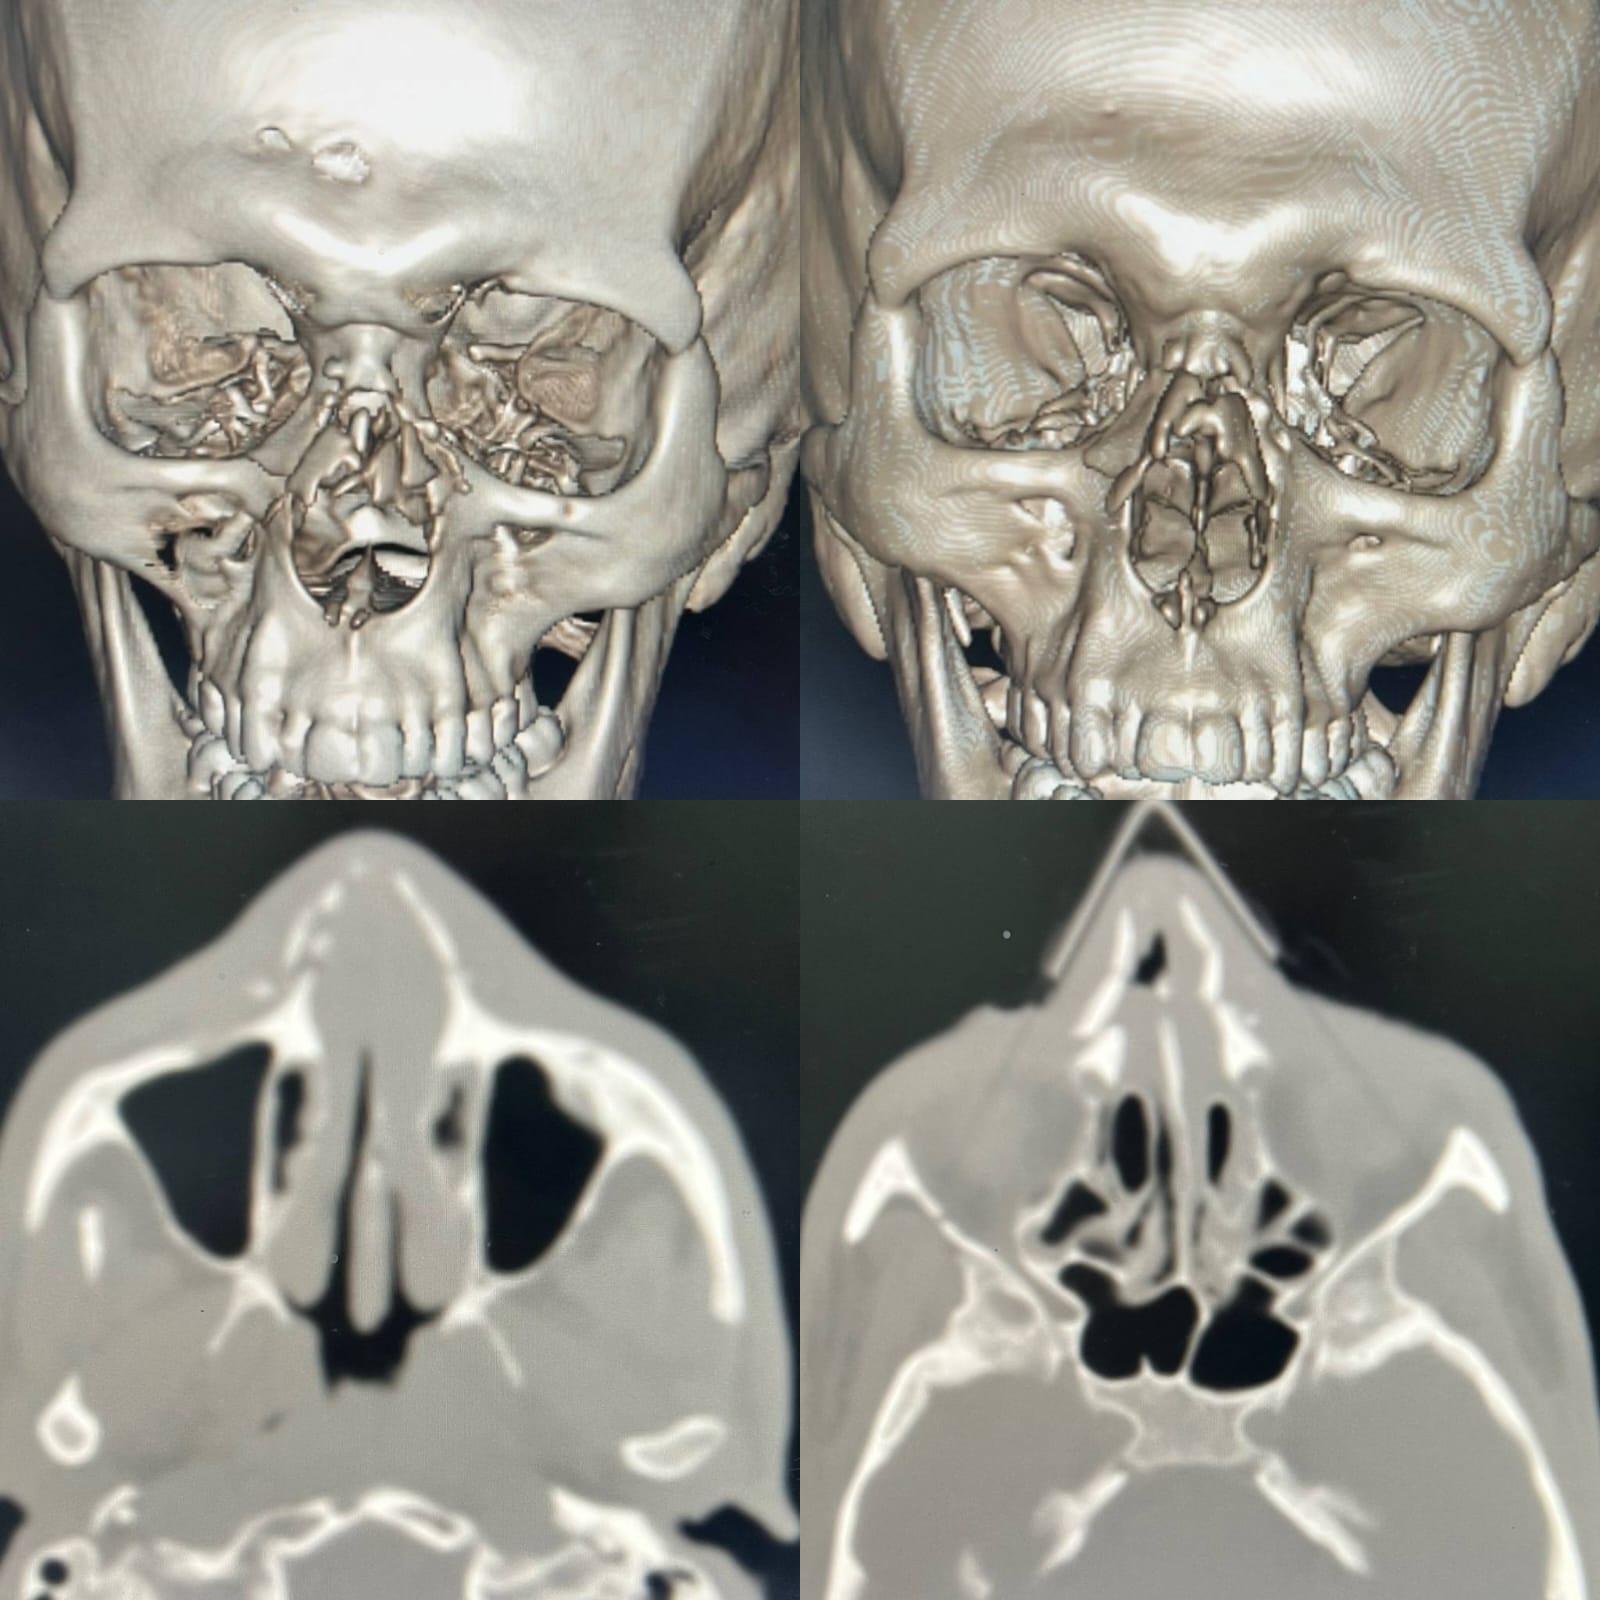

وأوضح وكيل الوزارة أن المريض وصل إلى قسم الطوارئ في حالة حرجة، حيث تبين وجود تهتك شديد بعظام وأنسجة الوجه، مع تضرر بالغ في معالم الأنف، واندماج بين مجريي التنفس والطعام، ما استدعى تدخلاً طبيًا عاجلًا لإنقاذ حياته.

ومن جانبه، أوضح الدكتور أحمد معتمد عامر، استشاري ورئيس قسم جراحة الوجه والفكين، أنه تم التعامل مع الحالة بشكل فوري، حيث جرى تأمين مجرى الهواء أولًا، ثم نقل المريض إلى غرفة العمليات لإجراء تدخل جراحي دقيق استمر نحو 5 ساعات متواصلة.

وأشار إلى أن الجراحة تضمنت فك الاندماج بين الفم والأنف، وإعادة بناء المسارات التشريحية الطبيعية، إلى جانب ترميم عظام الأنف والأنسجة الرخوة، بما أسهم في استعادة الشكل التشريحي للوجه، وفصل الوظائف الحيوية المتعلقة بالتنفس والكلام وتناول الطعام.

جانب من تشخيص الحالة